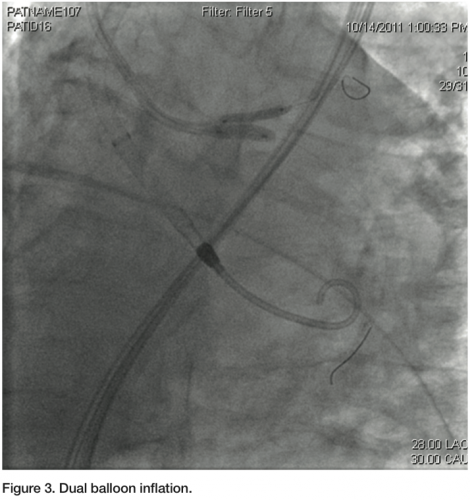

a Judkins left 3.5 guiding catheter was used to engage the left main. Two 0.014” angioplasty wires were introduced; one into the LAD, and one into the distal Cx. A 3.0 x 12 mm balloon was placed in the ostium of the Cx, and a diagnostic angiogram was obtained (Figure 1). Subsequently, a 2.5 mm balloon was placed from the left main into the LAD. A 3.5 x 8 mm bare-metal stent was placed in the proximal Cx. The 2.5 mm balloon was inflated to 10 atmospheres, protecting the left main and proximal LAD from plaque shifting during deployment of the Cx stent (Figure 2). The stent in the Cx was then withdrawn until it indented the left main balloon. The balloon in the left main was inflated for nearly a minute during this process, and the patient was completely asymptomatic. Systolic blood pressure did drop from about 130 mmHg to about 90 mmHg, but diastolic pressure was maintained due to support from the Impella 2.5 circulatory support device. Both balloons were then simultaneously inflated for about 25 seconds (Figure 3). The patient transiently developed global ST elevation and systolic hypotension, but remained asymptomatic. After both balloons were deflated, final images revealed excellent coverage of the ostial Cx lesion, with no significant compromise of the left main and LAD. Intravascular ultrasound (IVUS) analysis after stent deployment revealed a cross sectional area of 6.3 mm2 in the ostium of the LAD, with excellent visualization of the Cx stent in the ostium. At the conclusion of the procedure, the Impella 2.5 circulatory device was weaned off in the cath lab, and the 13 French sheath was removed, with the pre-placed sutures securing hemostasis. The right femoral sheath was also secured using a single Perclose Proglide device. The patient was uneventfully discharged home the following morning.